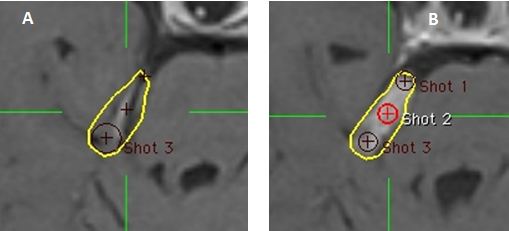

Hình 14: Hình (A) Lát cắt mặt phẳng dọc giữa của kế hoạch cho thấy đường đồng liều 50% (vàng) không bao phủ cực trên khối u (mũi tên). (B) Shot được thêm vào trung tâm khối u. (C) Giá trị z của shot thêm vào ở B điều chỉnh kế hoạch bao phủ cực trên khối u.

Bệnh nhân Đỗ Đức B.; nam, 52 tuổi. Chẩn đoán: U dây VIII (P). Chỉ định: xạ phẫu dao gamma quay (RGK) liều 14Gy”

Kỹ thuật 16: trọng số của các mỏm khối u